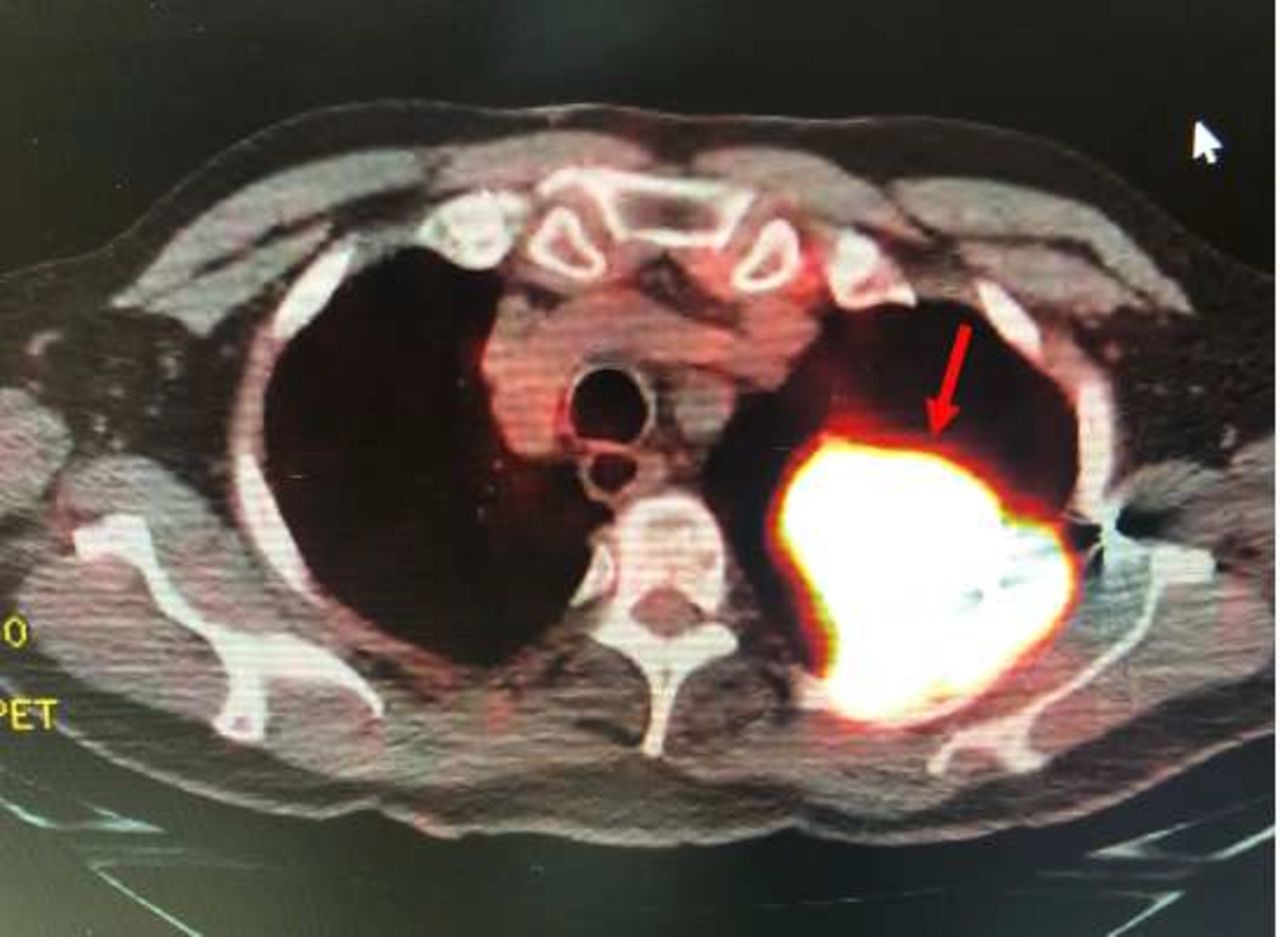

Позитронно-емісійна томографія чоловіка, на якій видно пухлину, клітини якої мають активний обмін речовин, через що й підсвічуються. Bartholomew et al. / BMJ Case Reports, 2025

Лікарі взяли зразки тканин із пухлини та з’ясували, що чоловік мав дрібноклітинний рак легень, який складає приблизно 15 відсотків усіх випадків раку легень. Обстеження не виявило в пацієнта метастазів у мозку чи інших органах, тому хірурги вирішили видалити пухлину під час операції. Хоча спершу чоловік одужував повільно, а також йому довелося обмежити активність через видалення значної частини легені, пацієнт перебуває в ремісії.